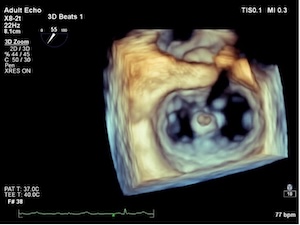

Multivalvular heart disease represents a less explored domain within cardiovascular surgery. In patients with aortic stenosis (AS) undergoing surgical or transcatheter aortic valve replacement (TAVR), the prevalence of moderate to severe mitral regurgitation (MR) ranges from 8% to 33%. Among the most common presentations are patients with severe AS and clinically significant functional MR. In instances of moderate surgical risk, open-heart surgery is typically performed, sometimes involving combined valve correction procedures. However, for patients deemed to be at high surgical risk or deemed inoperable, an interventional approach may be considered if the anatomy of both the aortic and mitral valves is conducive to such intervention. Careful analysis of each patient is essential in determining the appropriate treatment strategy, whether it involves isolated TAVR or if a staged intervention targeting the aortic and mitral valves is warranted. In the article, we present a review of the literature devoted to the strategy for bivalvular interventions in patients of high surgical risk and also a clinical case of a successful step-by-step interventional approach in an 83-year-old patient of high surgical risk with hemodynamically significant aortic and mitral valve disease, along with an analysis of the chosen approach.